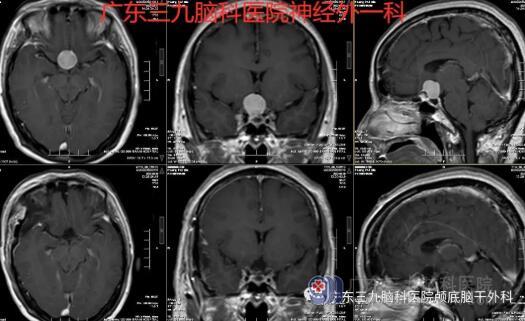

图3:术前术后MR示右侧额颞部呈术后改变,原鞍结节占位性病变已切除。